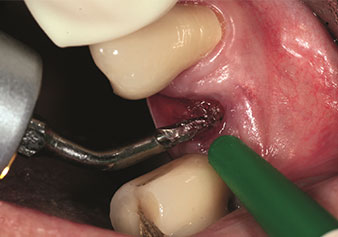

Alveolar management

One application, which is often underestimated is the atraumatic extraction of tooth roots or root fragments in the scope of alveolar management. The fine periotomes, which are currently available in two versions (EX1 and EX2 from W&H), can also be used to remove teeth which have previously undergone special endodontic treatment or ankylosed roots with ease. This results in extraction alveoli where both the hard and soft tissue are fully intact as it is generally possible to avoid reflection.

This establishes the optimal basis for subsequent or immediate implant treatment (Figures 1 and 2 included with the kind permission of Dr Torsten Conrad, Bingen a. Rhein).

Fine periotome (EX1 instrument)

Fig. 1: Fine periotome (EX1 instrument).

Photo: © Dr Torsten Conrad (Bingen a. Rhein)